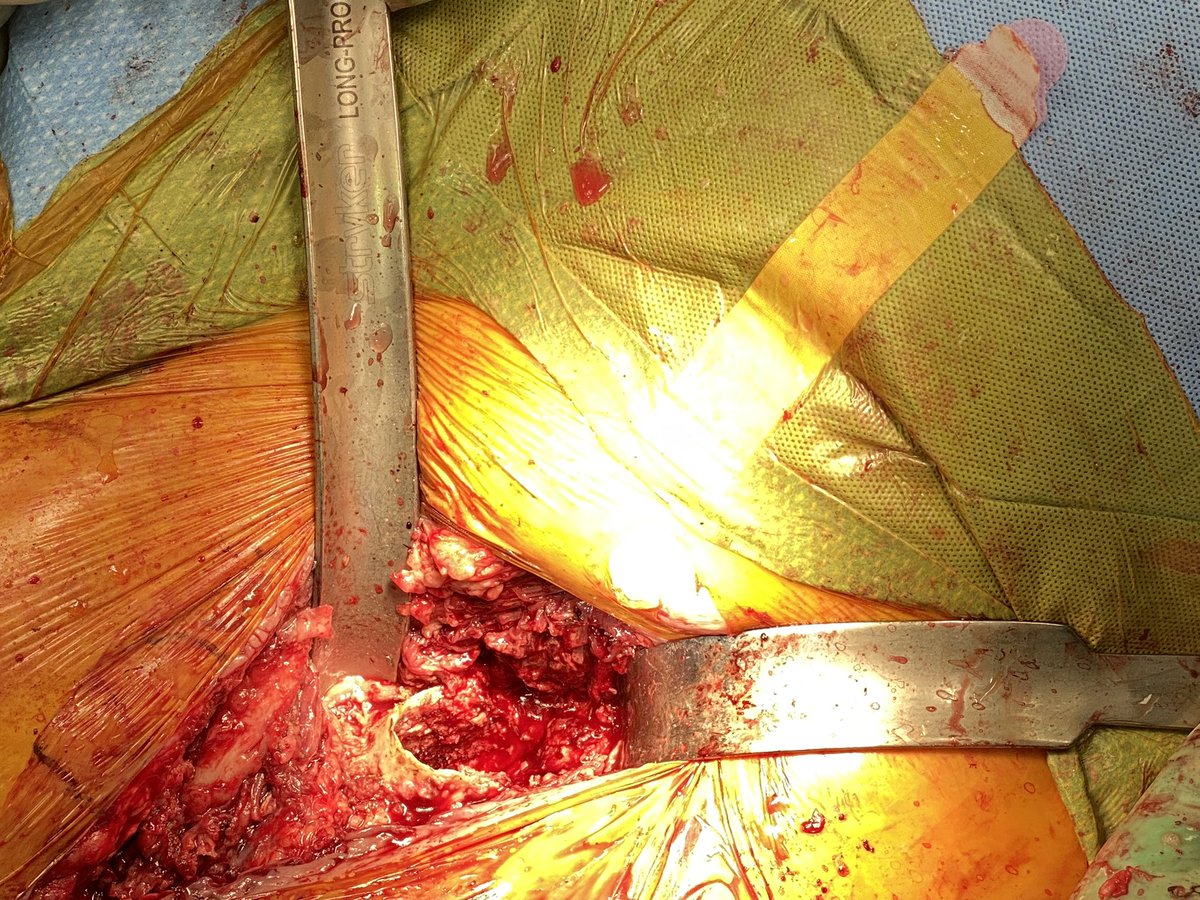

Thanks again @RiveraSurgical for incredible instruments. 5mins extraction and another no osteotomy day. Chronically infected left THA now with articulating spacer. Original surgery from DA approach so same approach used today. #orthotwitter #dofellowsneedETO’s